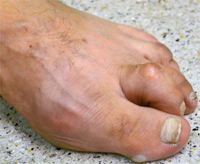

Beim Hallux valgus - im Sprachgebrauch häufig Ballenzehe genannt - handelt es sich um eine Abweichung der Großzehe nach außen, kleinzehenwärts. Diese Fehlstellung tritt häufiger bei Frauen auf. Die genaue Ursache ist nicht geklärt, sicherlich spielen falsches Schuhwerk und Erbanlagen eine große Rolle. Die unterschiedlichen Ausprägungen sind durch eine zunehmende Fehlstellung, verbunden mit Schmerzen, gekennzeichnet.

Von einer operativen Korrektur ohne Vorhandensein von Schmerzen, d. h. aus rein kosmetischer Sicht, ist abzuraten. Bei Auftreten von Schmerzen im Bereich der Großzehe ist die operative Vorgehensweise jedoch die einzig dauerhafte therapeutische Möglichkeit.